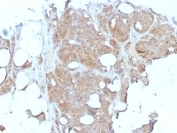

Major Vault Protein Antibody for IHC. Immunohistochemistry analysis of Major Vault Protein (MVP / LRP) expression in formalin-fixed, paraffin-embedded human testicular carcinoma using clone 1032 mouse monoclonal antibody. Tumor epithelial cells display strong cytoplasmic HRP-DAB brown staining with a granular to diffuse pattern, consistent with vault particle distribution, while surrounding stromal elements show minimal staining. The signal highlights malignant cell populations within glandular and solid tumor regions, supporting the role of Major vault protein in tumor biology and cellular stress response pathways.

Major Vault Protein Antibody for IHC. Immunohistochemistry analysis of Major Vault Protein (MVP / LRP) expression in formalin-fixed, paraffin-embedded human breast carcinoma using clone 1032 mouse monoclonal antibody. Tumor epithelial cells show moderate to strong cytoplasmic HRP-DAB brown staining with a diffuse pattern and focal granular accentuation, consistent with intracellular vault complex localization, while surrounding stromal and adipose tissues display minimal to low background staining. The signal highlights malignant epithelial cell populations within tumor nests, supporting the role of Major vault protein in tumor cell survival and cellular stress response pathways.

In immunohistochemistry applications, MVP is typically observed as cytoplasmic staining within epithelial cells, often displaying diffuse to finely granular patterns consistent with vault particle distribution. Perinuclear accentuation may be present, reflecting association with intracellular transport pathways. This staining pattern allows clear visualization of cell boundaries and cytoplasmic compartments, supporting detailed morphological interpretation in tissue sections.